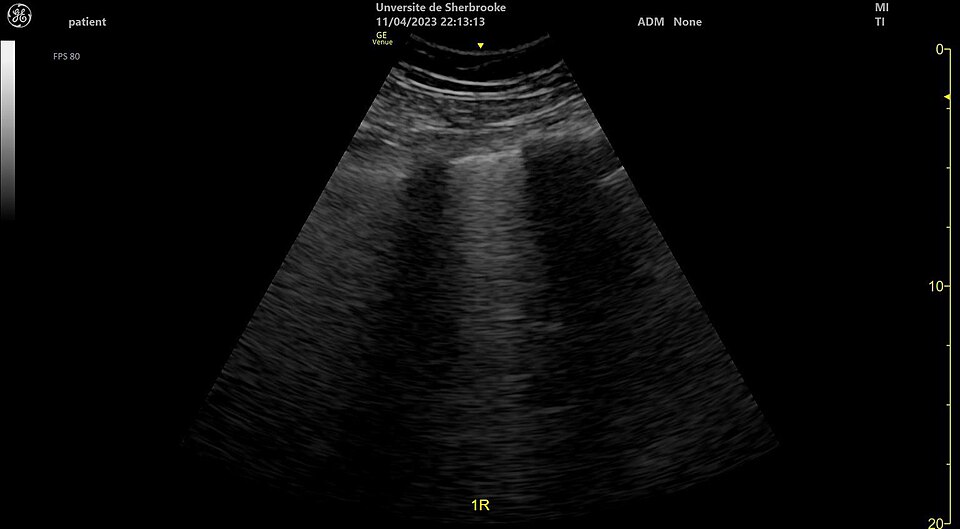

Lung Ultrasound — Wet Lung (Pulmonary Edema)

Ultrasound image showing wet lung appearance consistent with pulmonary edema

ULTRASOUND Downloaded 2026-03-15

Ultrasound

B Mode

Wikimedia Commons: Ultrasound wet lung 110303143856 1451430.jpg